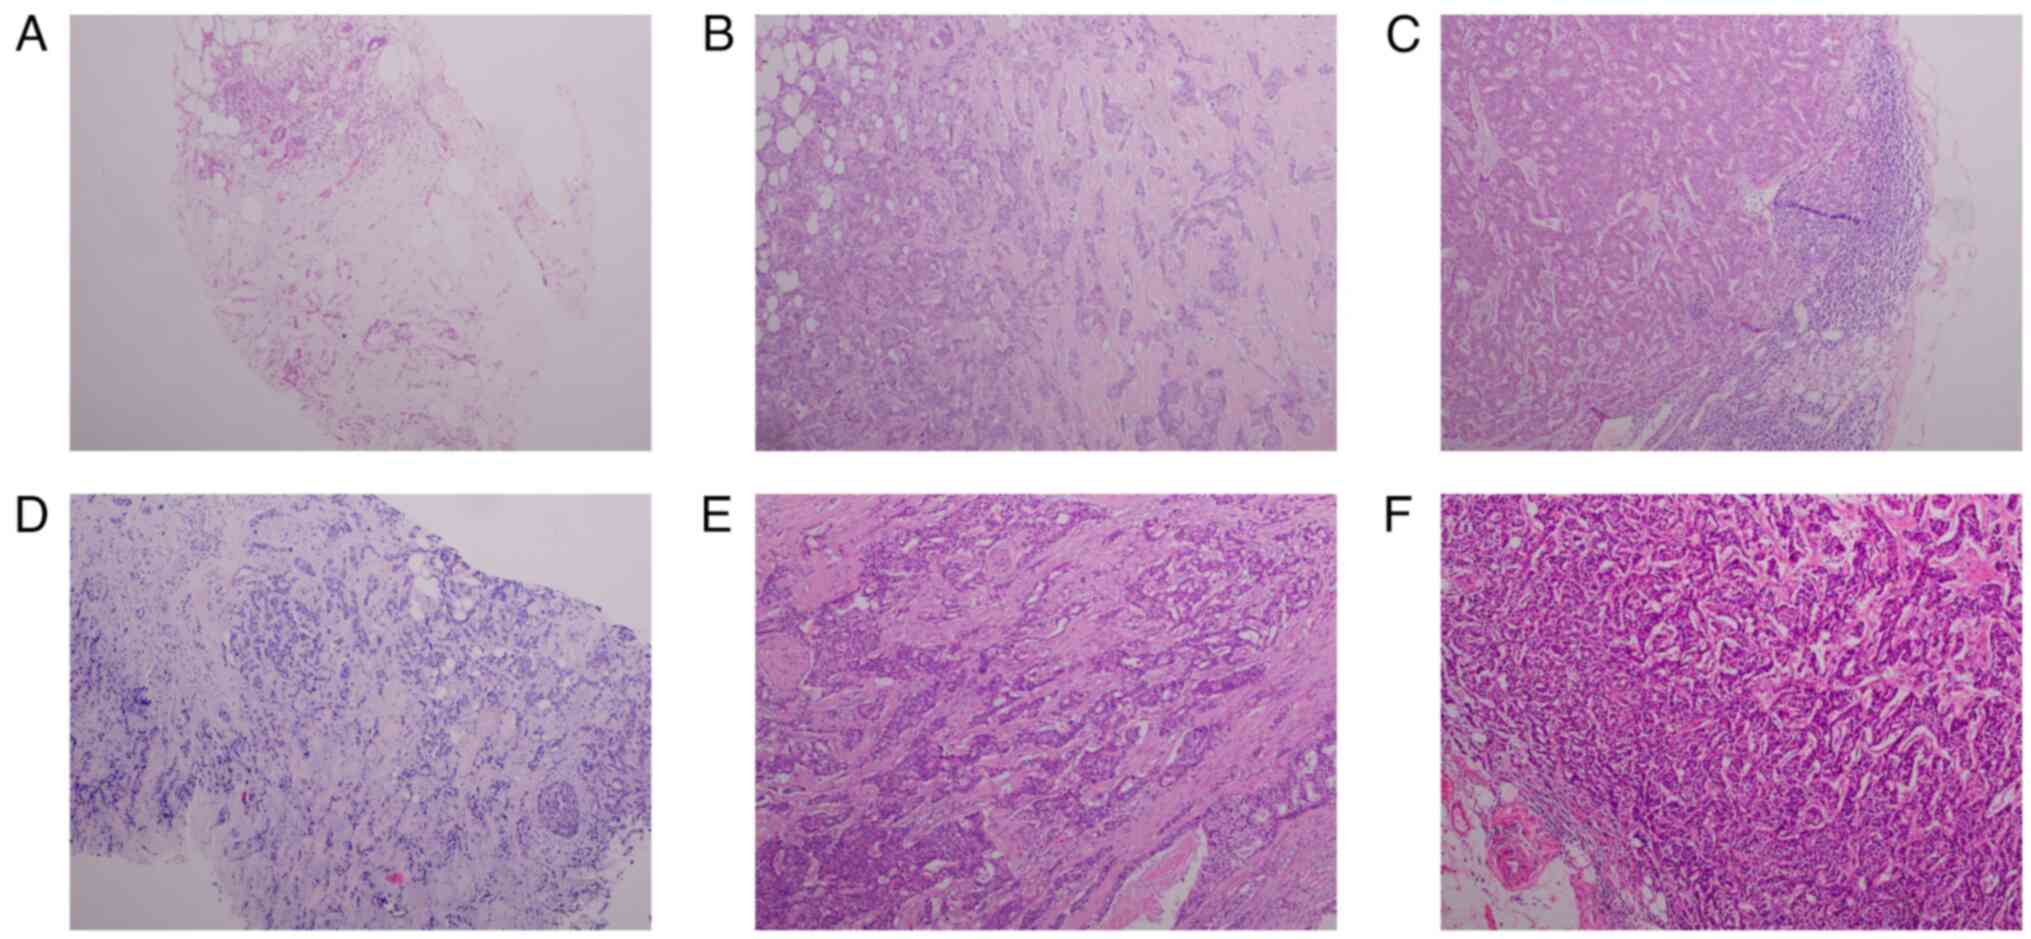

was confirmed on the basis of imaging and pathology tests (Fig. 1A) (14). Pathological testing was performed

and its location in a non-central area of the breast. Pathology and

immunohistochemistry (IHC) results confirmed a diagnosis of

invasive ductal carcinoma, grade II, with metastases found in 28/35

axillary lymph nodes (Figs. 1B and

C, and 2A-C), 13 days after admission, the

breast carcinoma (T4N0M1) in the right breast (Fig. 1D). The patient was treated with

chemotherapy in May. In May 2022, the updated pathology report of

the right breast revealed grade III invasive carcinoma, with

visible vascular embolus and nerve invasion. No cancerous tissues

were found in the nipple or the base margin. Carcinoma metastasis

was identified in all 23 axillary lymph nodes and in all 3 of the

other lymph nodes assessed (Figs.

1E and F, and 2D-F). CT scan showed multiple microscopic